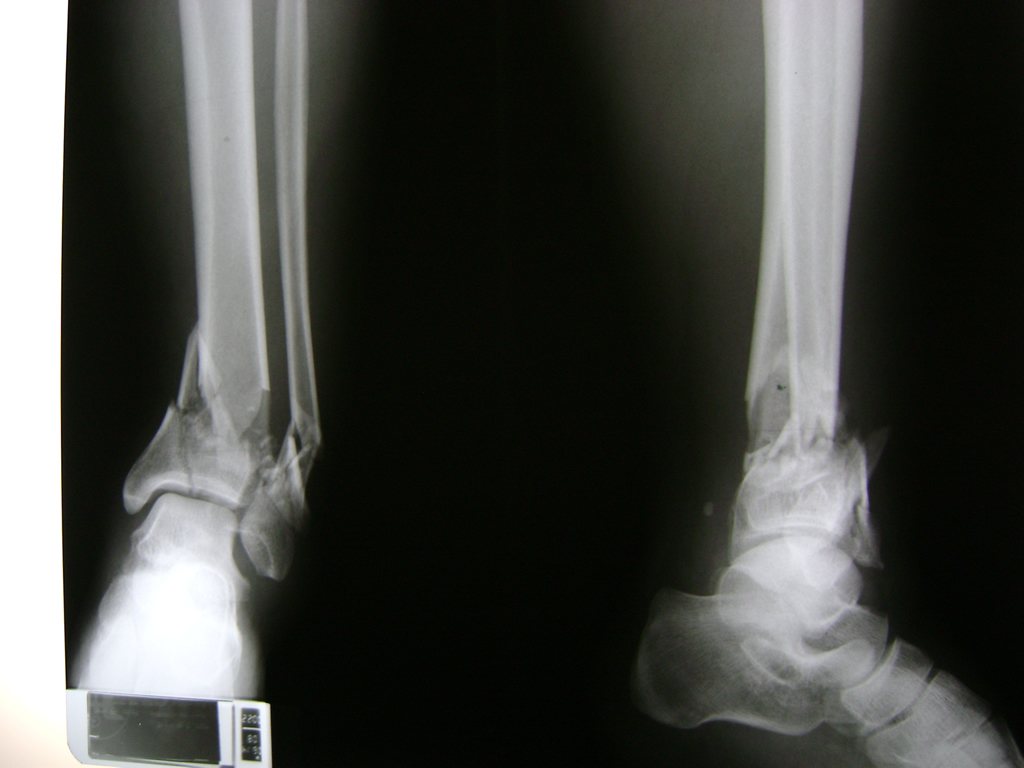

Una fractura de tobillo es la rotura de uno o más de los huesos del tobillo. Estas fracturas pueden ser:

- Parciales (el hueso está sólo parcialmente fisurado, no del todo).

- Completas (el hueso está perforado y está en 2 partes).

- Producirse en uno o ambos lados del tobillo.

Algunas fracturas de tobillo pueden requerir cirugía si:

- Los extremos de los huesos están desalineados entre sí (desplazados).

- La fractura se extiende hasta la articulación del tobillo (fractura intra-articular).

- Los tendones o ligamentos (tejidos que sujetan los músculos y los huesos entre sí) están rotos.